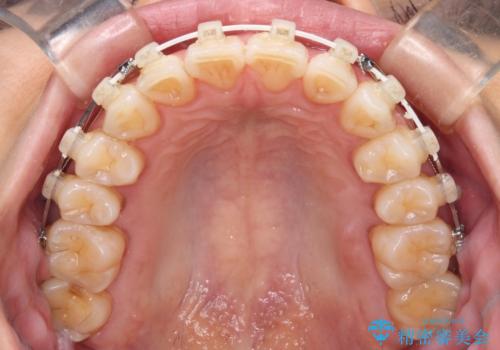

- 矯正装置

- 審美装置

- 奥歯の咬み合わせと、上下前歯の隙間を気にして来院された患者様です。

上顎の歯列全体が、下顎歯列に対して前方に位置しており、その影響で上顎前歯がやや前方に突出している状態でした。

横顔の印象から、抜歯をして積極的に口元を引っ込める必要はなかったため、アンカースクリューを用いて上顎歯列全体を後方に移動させることとしました。

奥歯の咬み合わせは理想的な状態に改善され、その結果として上下歯列もバランスの良い位置に収めることができました。

若干ではあるものの上顎前歯を内側に移動させることができ、以前よりも口が閉じやすいと感じるようになりました。